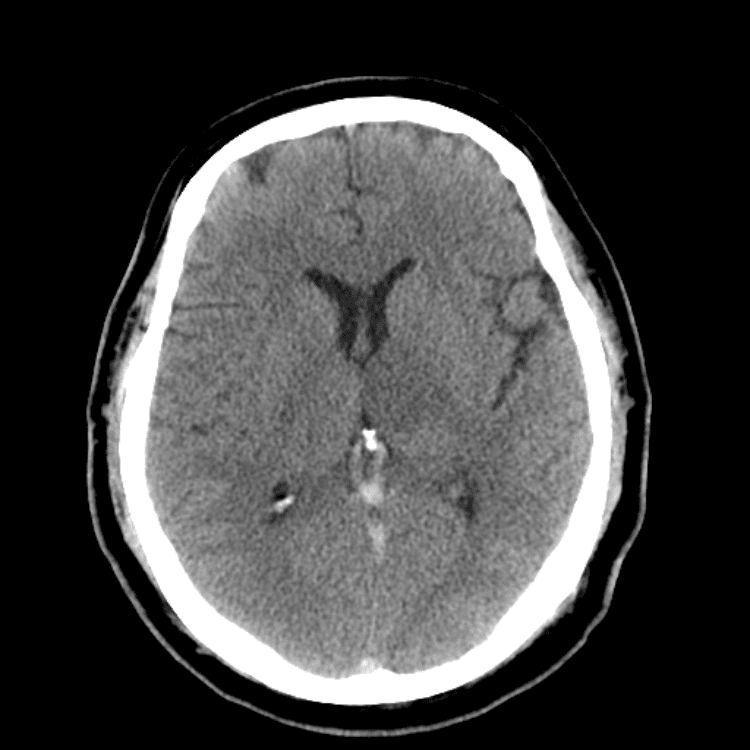

Nontraumatic Brain

Classic